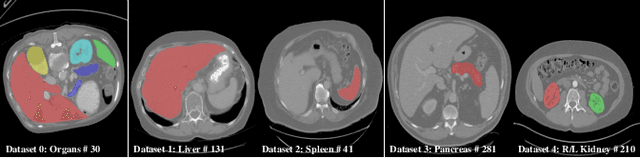

Abstract:There exists a large number of datasets for organ segmentation, which are partially annotated and sequentially constructed. A typical dataset is constructed at a certain time by curating medical images and annotating the organs of interest. In other words, new datasets with annotations of new organ categories are built over time. To unleash the potential behind these partially labeled, sequentially-constructed datasets, we propose to incrementally learn a multi-organ segmentation model. In each incremental learning (IL) stage, we lose the access to previous data and annotations, whose knowledge is assumingly captured by the current model, and gain the access to a new dataset with annotations of new organ categories, from which we learn to update the organ segmentation model to include the new organs. While IL is notorious for its `catastrophic forgetting' weakness in the context of natural image analysis, we experimentally discover that such a weakness mostly disappears for CT multi-organ segmentation. To further stabilize the model performance across the IL stages, we introduce a light memory module and some loss functions to restrain the representation of different categories in feature space, aggregating feature representation of the same class and separating feature representation of different classes. Extensive experiments on five open-sourced datasets are conducted to illustrate the effectiveness of our method.